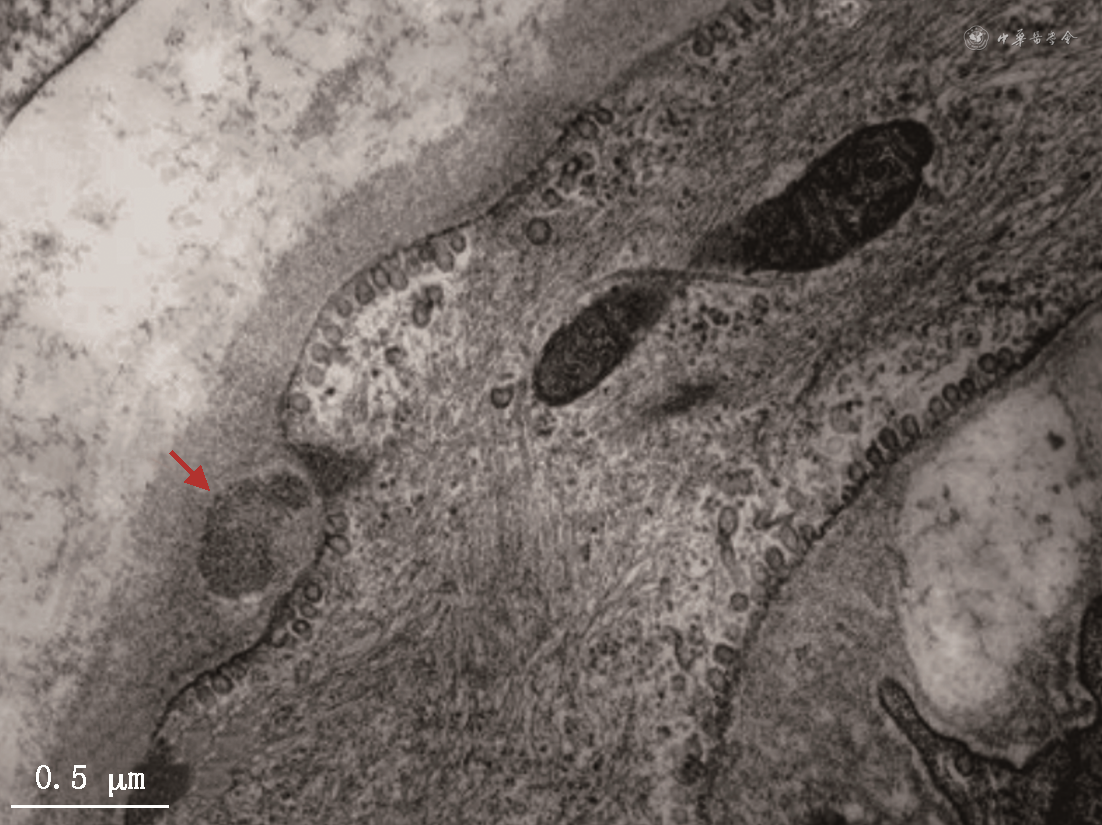

CADASIL主要累及全身微小动脉,在中枢神经系统主要累及小的穿支动脉和软脑膜动脉。电镜下可观察到血管平滑肌细胞变性、丢失,小动脉平滑肌细胞基底膜增厚和出现GOM结构。GOM通常呈直径1~2 μm的蘑菇状或不规则圆形,其底部与血管平滑肌细胞基底膜贴近,头部突向细胞外基质(图1)。毛细血管周细胞也可出现退行性改变,其表面也可出现GOM沉积。免疫电镜显示GOM中含有NOTCH3蛋白胞外段。

电镜下观察到皮肤小动脉血管平滑肌细胞基底膜出现GOM,可确诊为CADASIL。